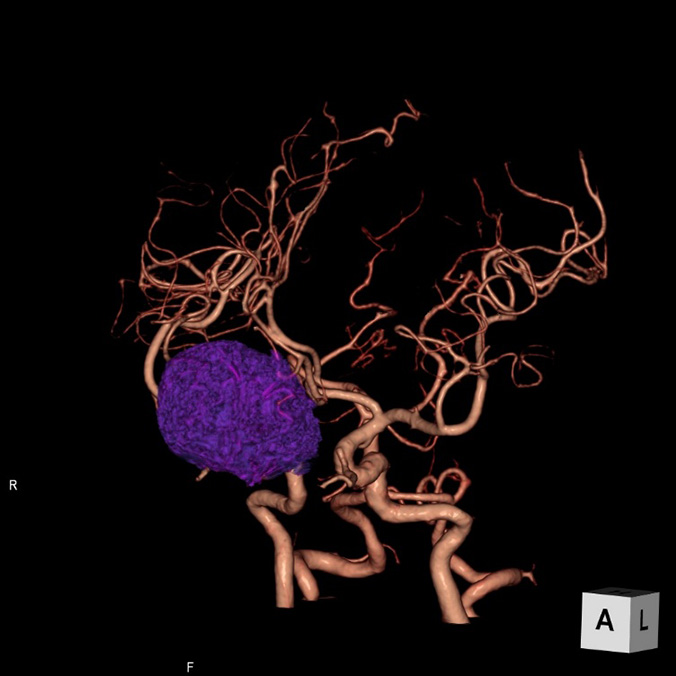

画像診断装置・放射線治療装置紹介

X線CT装置

64列 MDCT Aquilion CX (canon)

80列 MDCT Aquilion PRIME (canon)

80列 MDCT Aquilion PRIME SP(canon)

大きなトンネルの中に体を入れて、X線をあてて体の輪切りの写真を撮ります。CT検査には、単純CT検査と、造影剤を注射して撮影する造影CT検査があります。